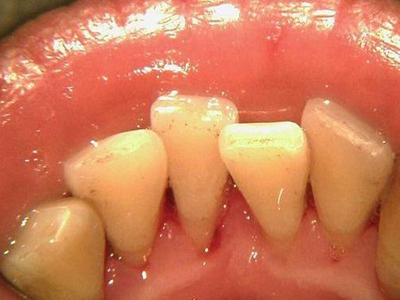

牙龈退缩牙根暴露出现黑斑图

牙龈退缩患者的上排多颗牙齿处的牙龈出现回缩,从而导致牙根外露,外露的牙根上存在黑色的牙菌斑、牙结石,伴有口臭、牙根面敏感等症状。